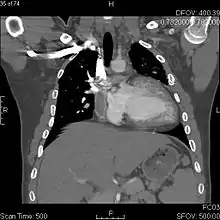

![]() Fontan procedure for tricuspid atresia | |